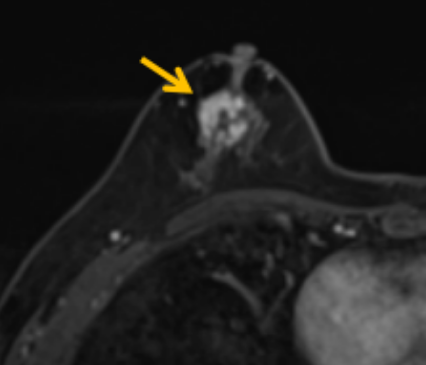

陳寶瑩評估圖像后發(fā)現(xiàn)病變?yōu)閮H僅在磁共振增強時顯示,為非腫塊樣病變,比較散,必須取得足夠多的組織才能確保病理檢查的準(zhǔn)確性,常用的核芯針活檢獲取的組織較少,因此最終確定了磁共振引導(dǎo)下行真空輔助抽吸旋切活檢。取得患者及家屬認(rèn)可后,陳寶瑩帶領(lǐng)團隊開始進行術(shù)前準(zhǔn)備。

針對患者乳房小固定難度大這一問題,陳寶瑩通過巧妙體位和固定器的調(diào)整,順利固定好乳房。經(jīng)過磁共振多模態(tài)掃描,陳寶瑩找出病變活性成分相對集中區(qū)域,精準(zhǔn)確定穿刺路徑,置入引導(dǎo)針、旋切針,到位后多角度旋切取出足量組織,拔除旋切針后即時行磁共振掃描,精準(zhǔn)取得組織且術(shù)區(qū)出血很少,遂加壓包扎,整個過程非常順利,旋切活檢后患者回家休息。兩天后隨訪,李女士沒有任何不適,五天后皮膚上幾毫米的小切口已經(jīng)愈合。最終病理結(jié)果證實為乳腺導(dǎo)管原位癌,為早期乳腺癌,為患者后續(xù)針對性治療奠定了基礎(chǔ)。